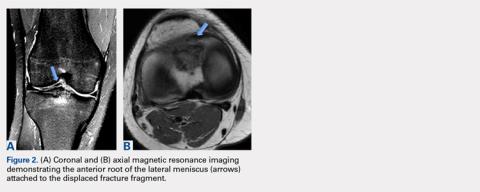

The fragment was located anterior and lateral to its native location, which created a mechanical block during knee motion. Additionally, MRI demonstrated that the anterior horn of the lateral meniscus was displaced and attached to the malunited fragment (Figures 2A, 2B) as well as to nonfunctional ACL fibers. On the basis of the mechanical block restricting extension and the displaced anterior horn of the lateral meniscus compromising meniscal function, we recommended arthroscopic surgery. After discussion of the risks and benefits of the procedure with the patient, she provided informed consent, and it was decided that the patient would undergo arthroscopic fragment excision followed by anatomic repair of the anterior root of the lateral meniscus, and that we would proceed with ACL reconstruction in the future given her subjective instability and physical examination findings of ACL insufficiency.Arthroscopic assessment of the right knee demonstrated the large osseous fragment located in the anterolateral aspect of the joint with the displaced anterior horn of the lateral meniscus attached as well as significant anterior impingement limiting knee extension. Probing of the anterolateral meniscal root in the lateral compartment showed abundant surrounding scar tissue with an abnormal attachment, representing a chronic root avulsion. A mechanical shaver was used to débride the scar tissue and expose the malunited fragment, followed by complete osseous fragment excision with a high-speed burr (Figure 3).